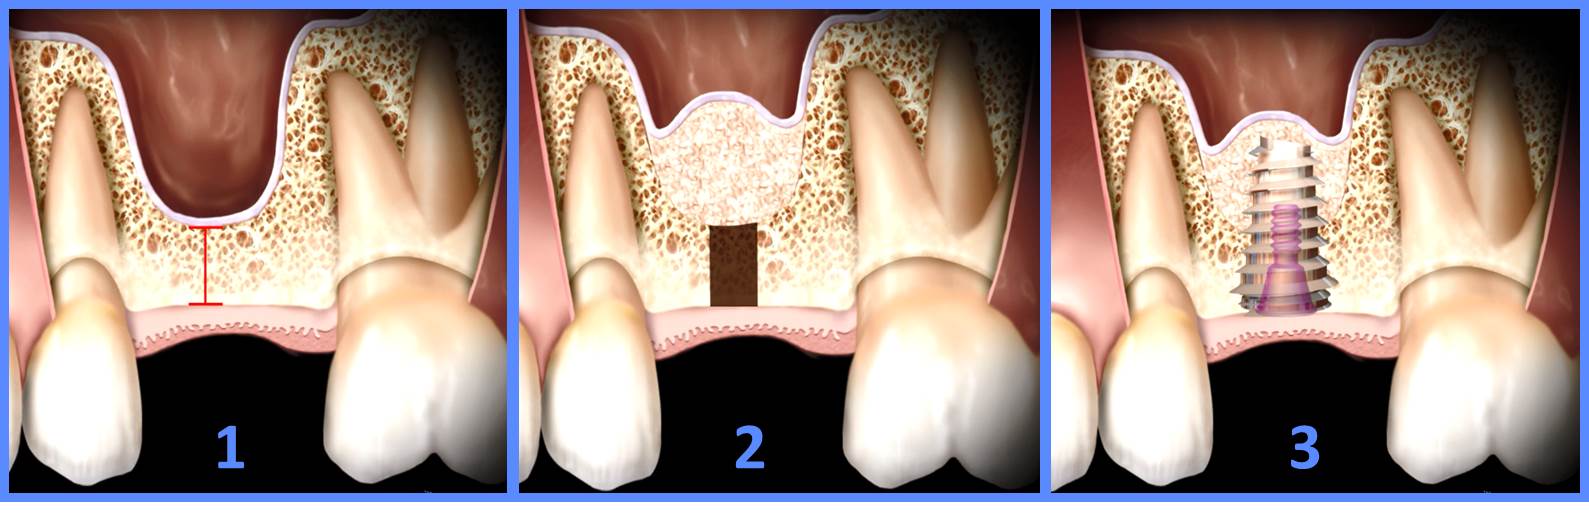

Le remplacement d’une dent se fait en plusieurs étapes

- Phase chirurgicale : Le chirurgien crée une cavité de la taille de l’implant ; ensuite il y insère l’implant.

- Pendant 6 mois l’implant va être intégré par l’os de la mâchoire (dans certains cas la durée peut être raccourcie à 4 ou 5 mois). Cette phase s’appelle l’ostéo-intégration : les cellules osseuse vont se fixer sur l’implant et reconstruire l’os solidement.

- Phase prothétique : Le dentiste ajoute le pilier, puis la couronne.